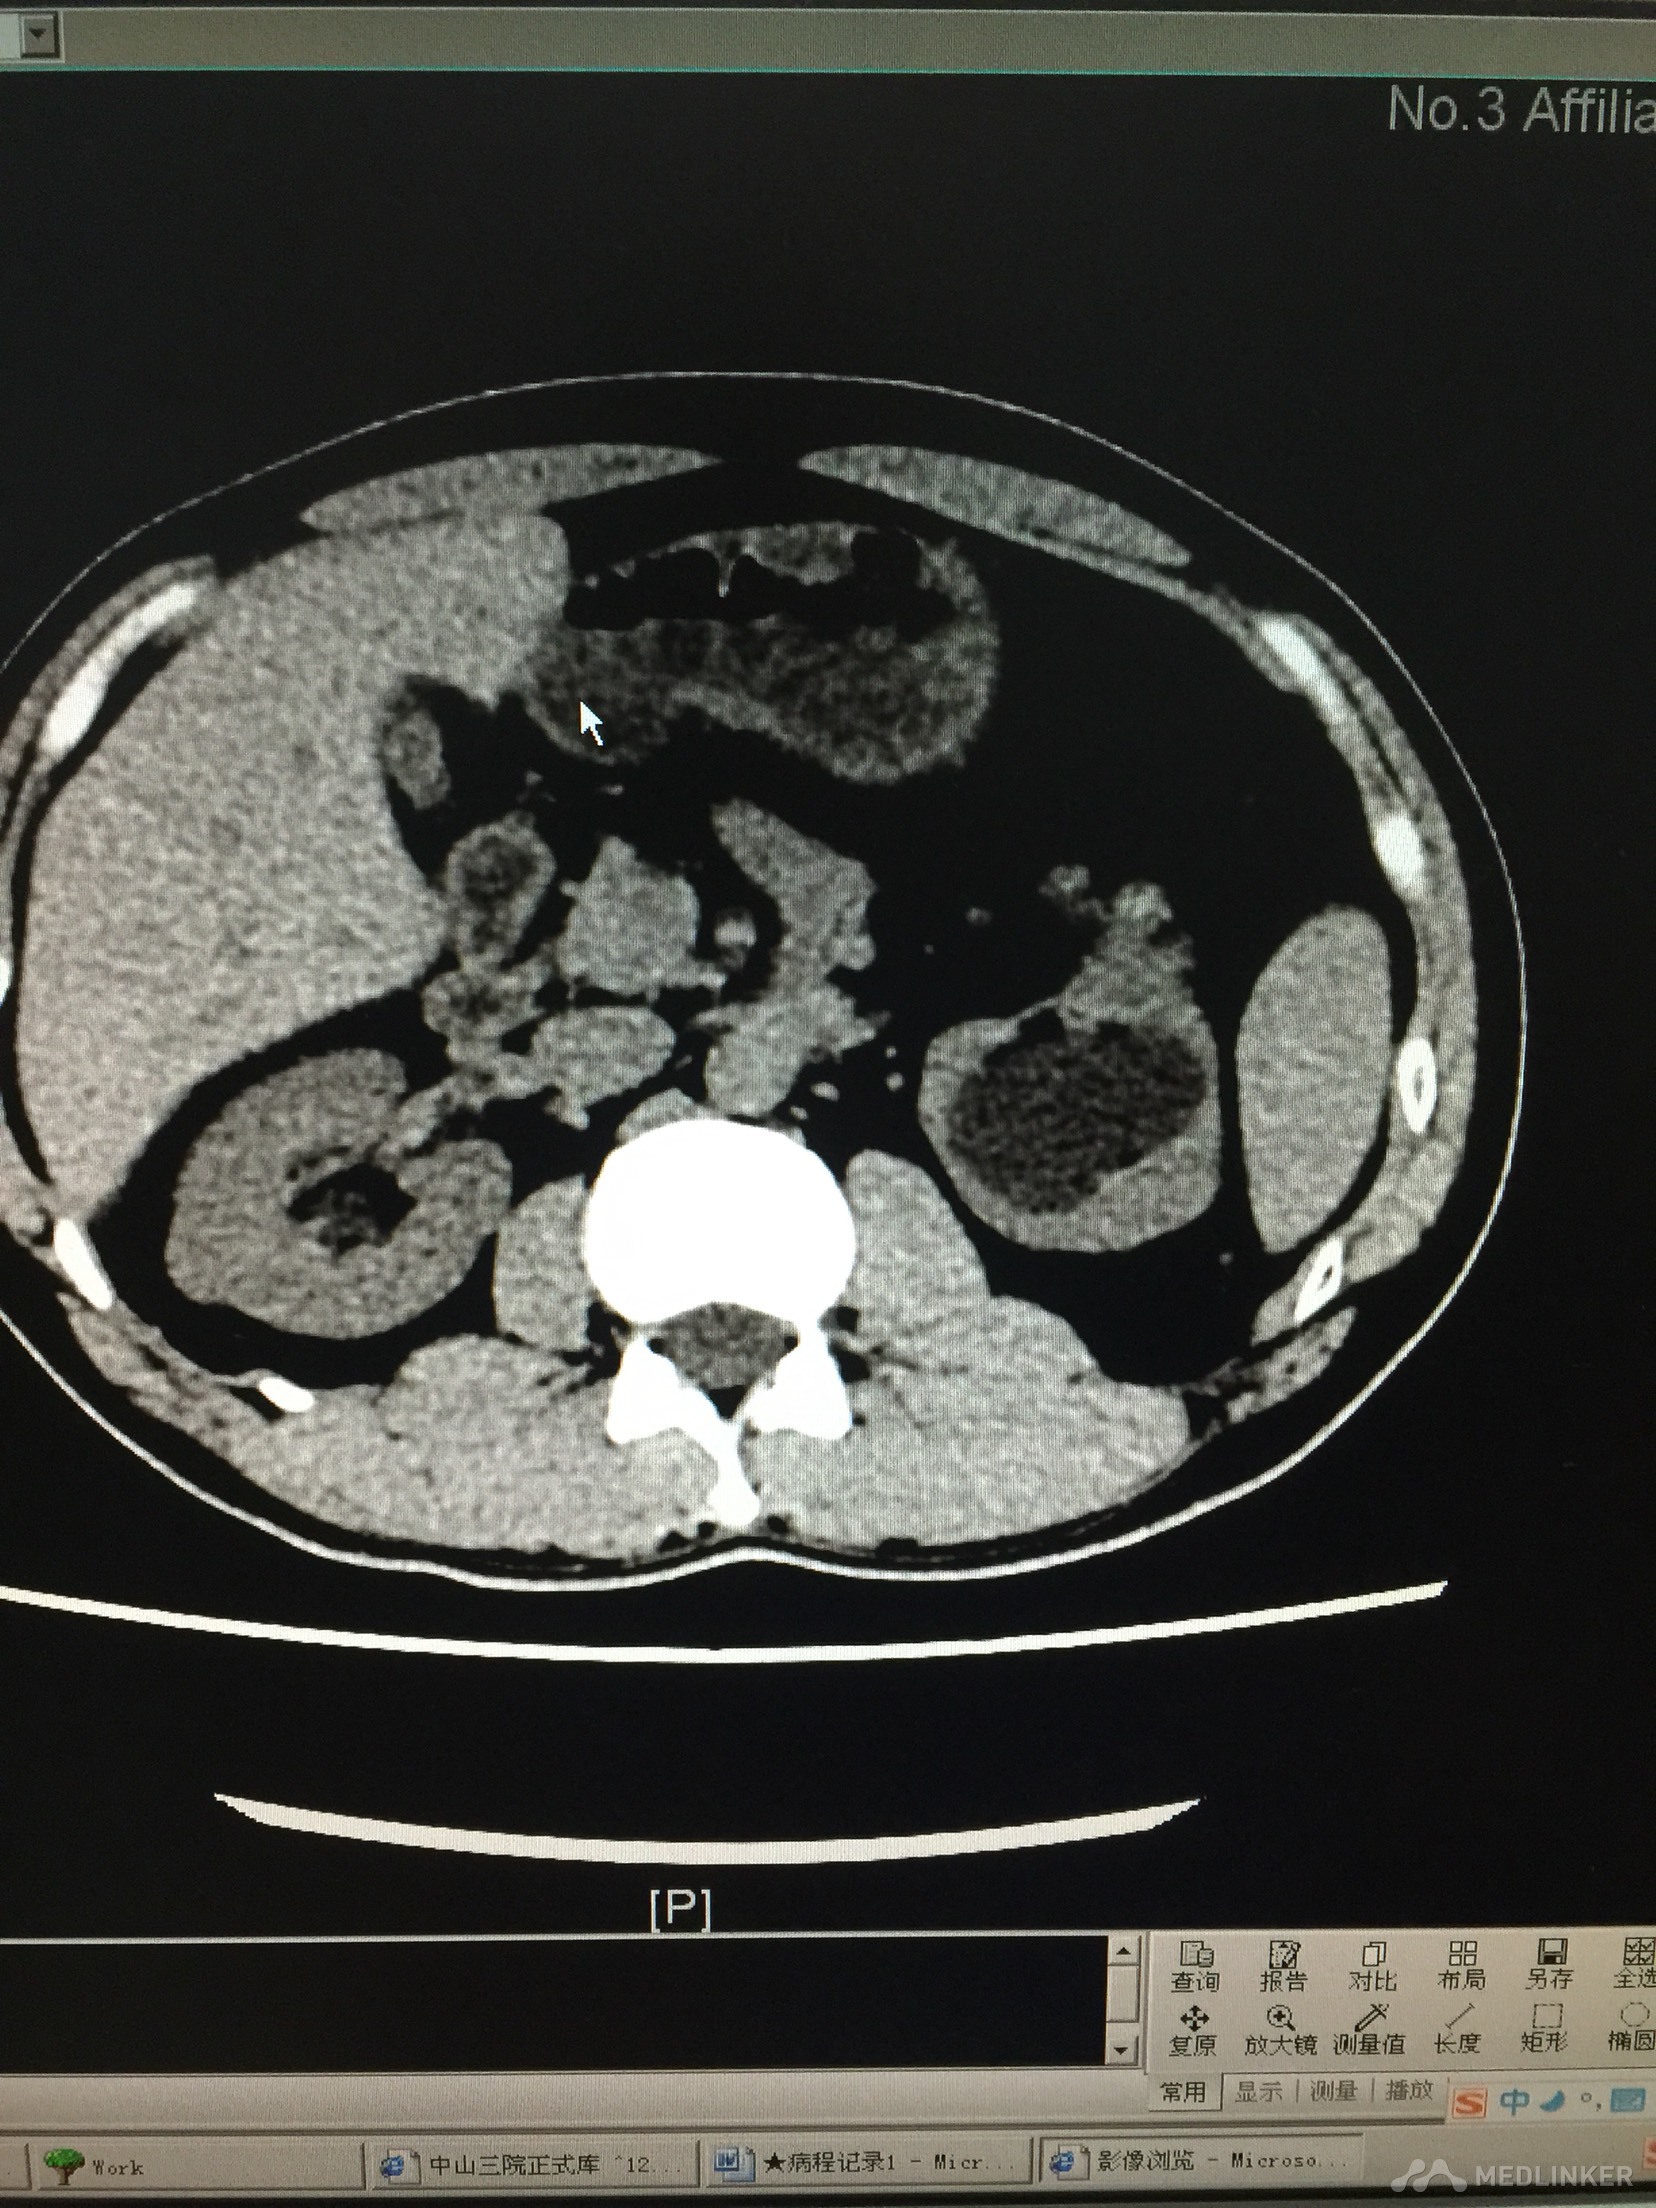

肾结石合并肾积水?

患者体检发现肾结石,但此时已经严重肾脏积水,患者诉并没有任何不适。为什么肾脏损害如此严重,症状却没有呢?